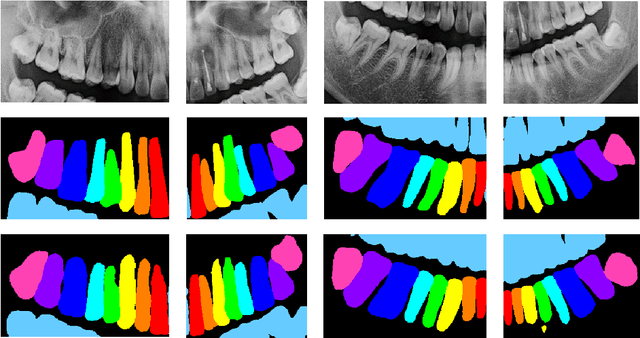

Abstract:Dental panoramic x-rays are commonly used in dental diagnosing. With the development of deep learning, auto detection of diseases from dental panoramic x-rays can help dentists to diagnose diseases more efficiently.The Dentex Challenge 2023 is a competition for automatic detection of abnormal teeth along with their enumeration ids from dental panoramic x-rays. In this paper, we propose a method integrating segmentation and detection models to detect abnormal teeth as well as obtain their enumeration ids.Our codes are available at https://github.com/xyzlancehe/DentexSegAndDet.